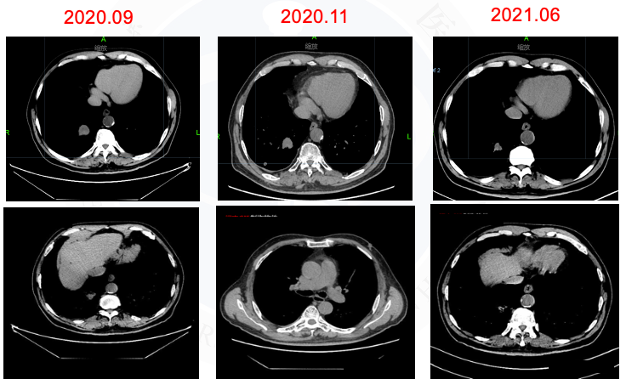

方案:经与患者及家属充分沟通后,2020.09月行厄洛替尼150mg qd+贝伐珠单抗 15mg/kg+左侧枕叶病灶SRS。

图5胸部CT

颅内及胸部病灶稳定半年以上,患者治疗意愿积极。

方案:2021.06行胸部放疗55Gy/5次。

√ 2021.06.28胸部CT:右肺下叶后基底段肿块约21×23×21mm大小,右肺下叶后基底段(Img230)见结节影,大小为7×7mm,较前缩小。疗效评价PR。

胸部稳定,未见进展。疗效评价PD。